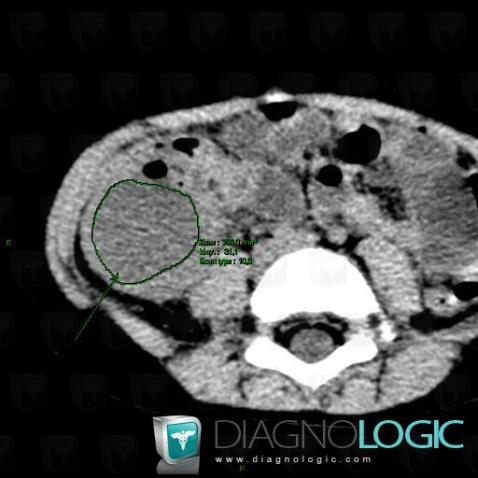

Abscess, Caecum / Appendix, CT

Here is the specific information in the key image above:

- Diagnosis Abscess, Location(s) Caecum / Appendix, with gamuts Appendiceal lesion, Cecal / lleocecal valve lesion, Pericecal fat infitration